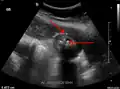

Right upper quadrant abdominal ultrasound is most commonly used to diagnose cholecystitis.[1][26][27] Ultrasound findings suggestive of acute cholecystitis include gallstones, pericholecystic fluid (fluid surrounding the gallbladder), gallbladder wall thickening (wall thickness over 3 mm),[28] dilation of the bile duct, and sonographic Murphy's sign.[13] Given its higher sensitivity, hepatic iminodiacetic acid (HIDA) scan can be used if ultrasound is not diagnostic.[13][14] CT scan may also be used if complications such as perforation or gangrene are suspected.[14]

Abdominal ultrasonography showing gallstones, wall thickening and fluid around the gall bladder -